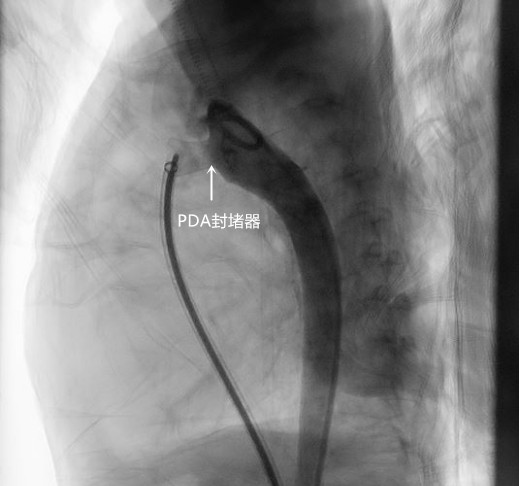

最终,刘丽萍副主任医师、刘震宇副主任医师克服重重困难为希希完成了这场艰难的手术,历时1.5小时。术后孩子生命体征平稳,直接回到病房术后观察。

手术第二天,希希父母开心的表示,从来都没有看见希希睡得这么安稳,以前用手放在胸口都可以感觉到的心脏杂音不见了,且手术穿刺点仅3mm,结痂脱落后几乎无疤痕。4天后希希顺利出院了。